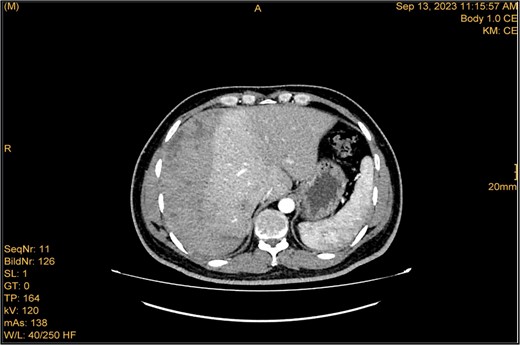

A 41-year-old male with a clear medical background, presented to the Emergency Department with right upper quadrant (RUQ) abdominal pain for two days, associated with fatty dyspepsia, anorexia, nausea, and vomiting. On arrival, his heart rate was 111 bpm with a blood pressure of 128/94 mmHg. On examination, a yellowish discoloration of skin and sclera was noted with a negative murphy sign. Investigations showed elevated liver enzymes (LFT). An initial abdominal ultrasound showed a distended gallbladder with a thickened wall and multiple stones, largest measuring approximately 1.4 cm, and a common bile duct measuring 5 mm (Fig. 1). A magnetic resonance cholangiopancreatography (MRCP) identified a tiny 4-mm mid-cystic duct stone without intrahepatic biliary dilatation. After the initial management, an emergency LC was performed, which posed minimal challenges. Fortunately, no intraoperative complications were reported. A drain was kept in the subhepatic area, and the patient was kept under close observation. Second day postoperatively, the patient experienced dizziness and an intense RUQ pain despite proper analgesia. His heart rate was 89 bpm with a blood pressure of 107/64 mmHg. Investigations showed a drop in hemoglobin level from 13.8 to 9.9 g/dl. An abdominal ultrasound showed a right subcapsular heterogeneous collection with a scalloped liver surface (Fig. 2). Therefore, an initial diagnosis of ISH post-LC was considered. Following the initial fluid resuscitation and blood transfusion, a further decline in hemoglobin level was noted reaching 8.8 g/dl. Further blood transfusion was commenced achieving stabilization. Further CT scan showed subcapsular hepatic hematoma measuring 7.1 × 19 × 21 cm, in its transverse, anteroposterior, and craniocaudal diameters, respectively, with no evidence of active extravasation (Fig. 3) confirming the final diagnosis of ISH post-LC. A multidisciplinary decision was made to continue conservative management after a proper explanation of the potential risk of sudden rupture of hematoma. The patient’s clinical condition and hemoglobin level, in addition to drain output, were meticulously monitored in the general ward, ensuring early detection of deterioration. Four days later, a follow-up CT scan revealed no new significant interval changes (Fig. 4). Nine days postoperatively, the patient was discharged with a follow-up appointment, which showed almost complete resolution.

Enhanced CT scan utilizing bleeding protocol. Status post-LC identified significant ISH with internal hyperdensity measuring 7.1 × 19 × 21 cm, in its transverse, anteroposterior, and craniocaudal diameters, respectively. Adjacent hyperemic liver parenchyma with intraparenchymal hematoma noted at segment 5, measured 4.7 × 4 × 4.7 cm. Intraparenchymal hypodensities noted at segments 8 and 4b, likely represent hepatic contusions and lacerations. No evidence of active contrast extravasation.